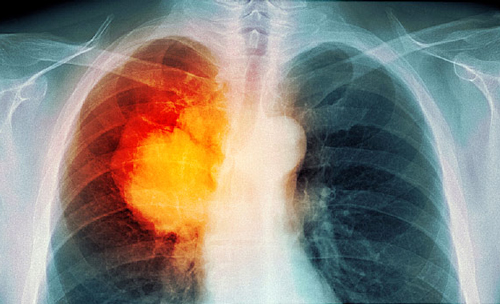

Pulmonary fibrosis is a progressive disease caused by the scarring of injured lung tissue. The scar tissue that developed on the organ is thicker and stiffer than healthy tissue.

Fibrosis hampers the normal expansion and contraction of the lung. This reduces the amount of oxygen that could be drawn with each breath, which in turn decreases the amount of oxygen available for use by the body.

There are lung cancer patients who experience pulmonary fibrosis after getting exposed to radiation, such as during thoracic radiotherapy treatment. Other patients suffering from different types of cancer develop this lung condition after taking Bleomycin (Blenoxane), a pharmaceutical drug used for chemotherapy.